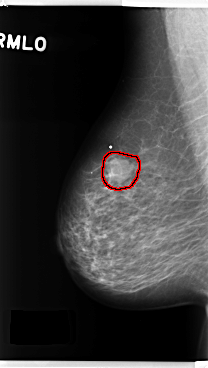

C_0278_1.RIGHT_MLO

FILE: C_0278_1.RIGHT_MLO.OVERLAY

TOTAL_ABNORMALITIES 1

ABNORMALITY 1

LESION_TYPE MASS SHAPE ROUND MARGINS MICROLOBULATED

ASSESSMENT 4

SUBTLETY 5

PATHOLOGY BENIGN

TOTAL_OUTLINES 1

BOUNDARY